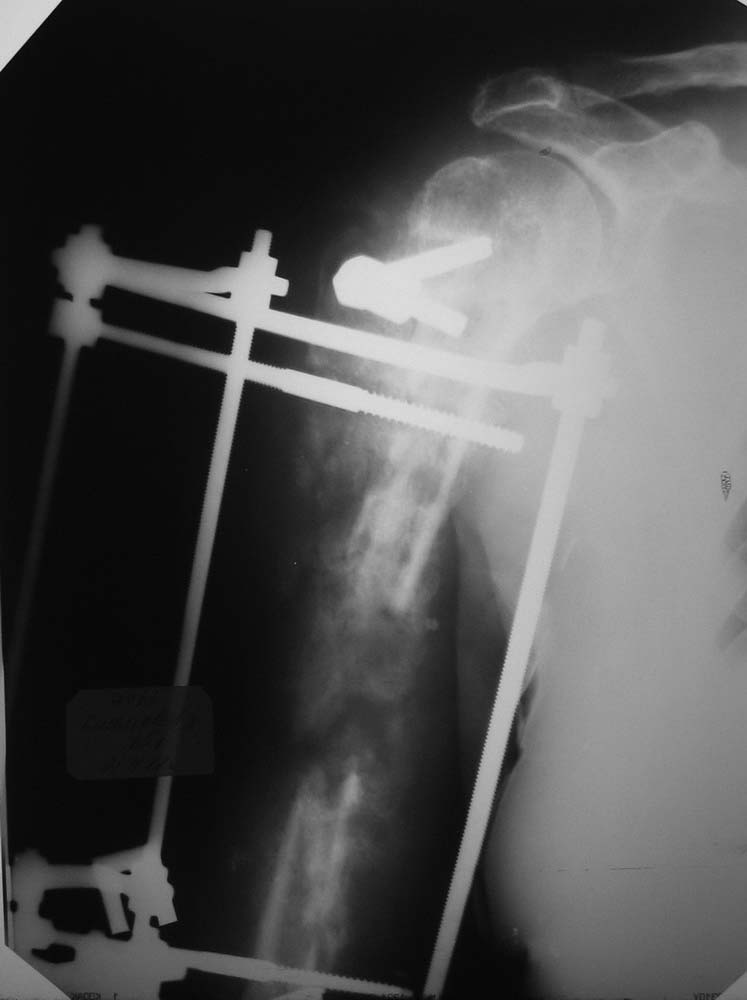

Последний R-снимок - со стержневым аппаратом.

Виктор! Начну с вопроса - что остановило первично заштифтовать, а не идти открыто? При такой установке пластины, Вы сразу дали шанс сломаться всему повторно. Если оставлять в аппарате, то срастаться будет лет так надцать (дефект около 10 см). Сохраните длину конечности и синтезируйте штифтом, ранняя нагрузка и штифт будет выполнять у Вас роль внутреннего эндопротеза и пусть срастается, главное будет рабочая рука, а не красивый рентген снимок.

Сейчас ситуация, конечно, гораздо интереснее, чем была. Для оценки и планирования желательно бы увидеть обе проекции сверху донизу.

Вариантов тут довольно много, интрамедуллярный остеосинтез, наверно, в каком-то из воплощений обеспечил бы максимально быструю независимость пациента и возможность движений в суставах. Например, можно на пару недель установить санирующий спейсер, а потом перейти на Fixion. Или сделать сразу блокируемый штифт с антибиотиковым покрытием. Или неблокируемый, но тоже с цементом. Зависит в т.ч. от состояния отломков на всем протяжении, чего пока не видно.